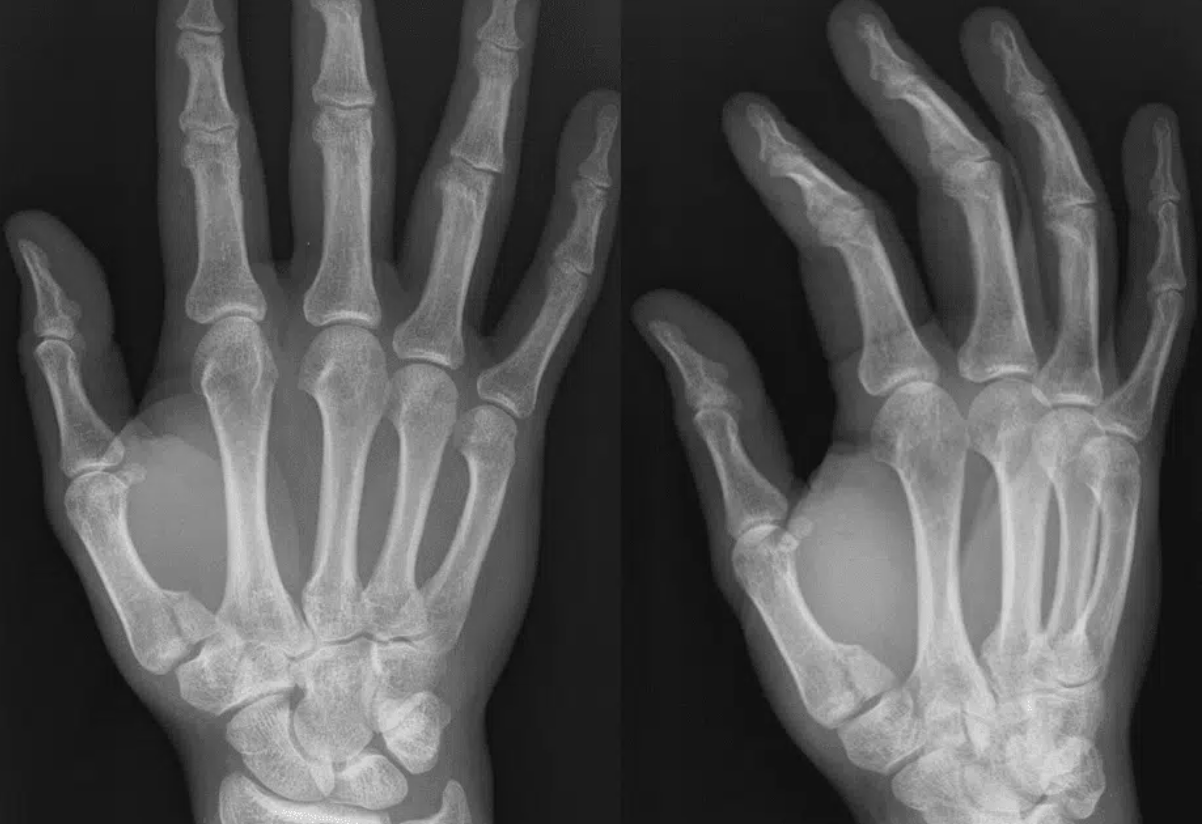

• RADIOLOGY: BENNET FRACTURE

• A close-up of a handDescription automatically generated

• Fracture dislocation of base of metacarpal

• TX: Thumb spica and RICE